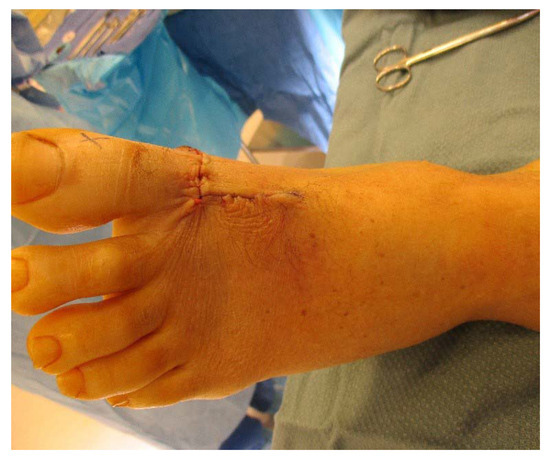

A Novel Technique for Soft-Tissue Defect Repair After Traumatic Rupture of the Extensor Hallucis Longus Tendon

by Ellianne Nasser, William Clark and Michael Gibboney

J. Am. Podiatr. Med. Assoc. 2021, 111(3), 18066; https://doi.org/10.7547/18-066 - 1 May 2021

Background: Surgical repair of extensor hallucis longus (EHL) tendon rupture with a concomitant capsular defect has not been reported in the literature. This case presents a novel approach to EHL tendon rupture repair along with repair of a first metatarsophalangeal joint capsule defect. [...] Read more.

Background: Surgical repair of extensor hallucis longus (EHL) tendon rupture with a concomitant capsular defect has not been reported in the literature. This case presents a novel approach to EHL tendon rupture repair along with repair of a first metatarsophalangeal joint capsule defect. Methods: A case study is presented of a 61-year-old man with a traumatic EHL tendon rupture and capsular defect treated with an EHL tendon turndown flap and tenodesis to the extensor hallucis brevis and capsularis tendons with autograft flap reconstruction of the first metatarsophalangeal joint capsule. Discussion: A 61-year-old man presented with an acute traumatic EHL tendon rupture and first metatarsophalangeal joint capsule compromise after a chainsaw injury. He subsequently lost dorsiflexion of his hallux, and magnetic resonance imaging confirmed a 2.2-cm gap in the EHL tendon. He was treated with an EHL tendon turndown flap and tenodesis to the extensor hallucis brevis and capsularis tendons to reestablish dorsiflexion to the hallux. The injury was noted to infiltrate the first metatarsophalangeal joint capsule and was treated with an autograft of the first metatarsophalangeal joint capsule for a capsular defect. At 1-year follow-up the patient has regained dorsiflexion of the hallux and is back to activities such as snow skiing without pain. Conclusions: Ruptures of the EHL tendon with first metatarsophalangeal joint capsule defects have not been reported in the literature. Herein, a novel approach was used to reestablish physiologic function to the EHL tendon and provide sufficient coverage of the first metatarsophalangeal joint. (J Am Podiatr Med Assoc 111(3): 1-5, 2021) Full article